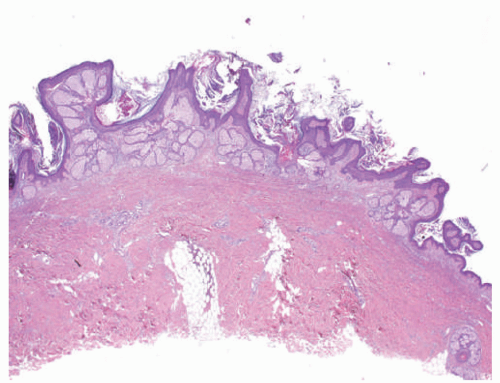

![]() FIGURE 23-2. Epidermal nevus frequently resembles seborrheic keratosis histologically, with orthokeratotic hyperkeratosis, papillomatosis, and epidermal acanthosis. |